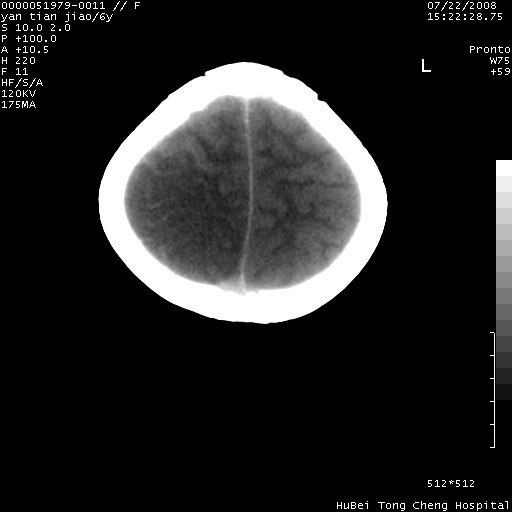

患儿 女,6岁。发热三天,昏迷五小时伴抽搐一次入院。pe:神志不清,浅昏迷状,双侧瞳孔不等大(右侧瞳孔直径3.5mm,左侧瞳孔2.0mm),对光反射迟钝,项强约一指,脑膜刺激征及病理反射阳性;双肺可及痰鸣音;四肢肌张力不高。

临床诊断:病毒性脑膜脑炎并脑疝?

颅脑ct轴位平扫,如下图:

大面积低密度区,可疑脑炎,建议强化!

结合临床症状,符合右颞顶枕叶病毒性脑膜脑炎.建议增强或mri。

右侧低密度区结合临床考虑脑炎